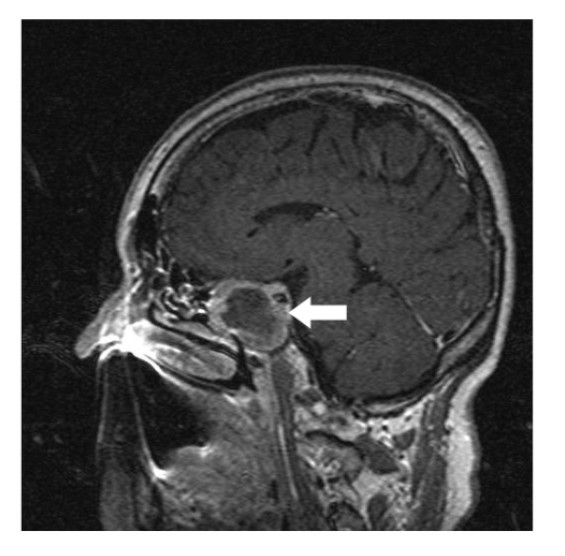

A 64-year-old lady presented to the outpatient department with complaints of headache and right eye blurring of vision for one month. Neurological examination revealed that bitemporal hemianopsia and impairment of visual acuity. Findings from fundus examination were within normal limits. Rest of the brain appeared unremarkable. Endocrine evaluation was normal. Results of renal function tests, liver function tests and haemogram test were within normal limits. A clinical diagnosis of non-secretory pituitary adenoma was made. Magnetic resonance imaging showed a well-circumscribed contrast-enhancing lesion in the sella (Figure 1, Figure 2). The patient underwent an endoscopic endonasal/transsfenoidal surgery in the supine position and total lesion resection was peformed. Intraoperatively, the lesion was found to be yellow colour, soft and avascular and it was removed totally until the sella turcica was visualized (Figure 3).In histopathologic examination septate hyphae were observed between inflammatory cells, Grocott staining is positive, but acid-fast stain for acid-fast bacilli (AFB) was negative. Histopathological findings suggest that infection of Actinomyces (Figure 4, Figure 5). We performed to patient consulted by patients to infectious diseases clinic. Patients underwent intravenous 6x2 gr ampicillin for four weeks.Then oral 4X500 mg amoxicillin treatment is planned a for at least 6 months. Patient did not have any deficits in the next six months.

Figure 1.White arrow shows on sagittal section of MRI that a well-circumscribed contrast-enhancing lesion in the sella

Preoperative diagnosis of pituitary abcess is difficult because the presenting symptoms in these patients are similar to that in patients with pituitary adenomas 4. The most common symptoms are headache, vision disturbances and endocrinological abnormalities 5. Magnetic resonance imaging is the best imaging modality for sellar abscess and the features include a hypo- or iso-intense sellar mass on T1-weighted sequences and a hypointense mass on T2-weighted sequences pituitary abscesses may be divided into primary and secondary types. Primary pituitary abscesses occur within a previously healthy gland, while secondary abscesses arise within an existing lesion, such as an adenoma, craniopharyngioma, or Rathke's cleft cyst. Secondary abscesses share radiologic characteristics with the lesions from which they arise. The typical primary pituitary abscess gives the same or slightly lower signal than brain on T1-weighted images, and could be mistaken for a solid mass or presumed to represent a pituitary adenoma. Contrast-enhanced images are useful, demonstrating absence of central enhancement, suggesting a fluid or necrotic center 6.Actinomyces brain abscess is usually diagnosed based on the contrast enhancement on the periphery as in this case.Also MRI spectroscopy findings are the described in actinomyces infection 7, 8.